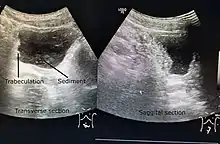

Ultrasound imaging can give information on the shape of the bladder, post-void residual volume, and evidence of kidney damage such as kidney size, thickness or ureteral dilation.[8] Trabeculated bladder on ultrasound indicates high risk of developing urinary tract abnormalities such as hydronephrosis and stones.[9] A voiding cystourethrography study uses contrast dye to obtain images of the bladder both when it is full and after urination which can show changes in bladder shape consistent with neurogenic bladder.[8]